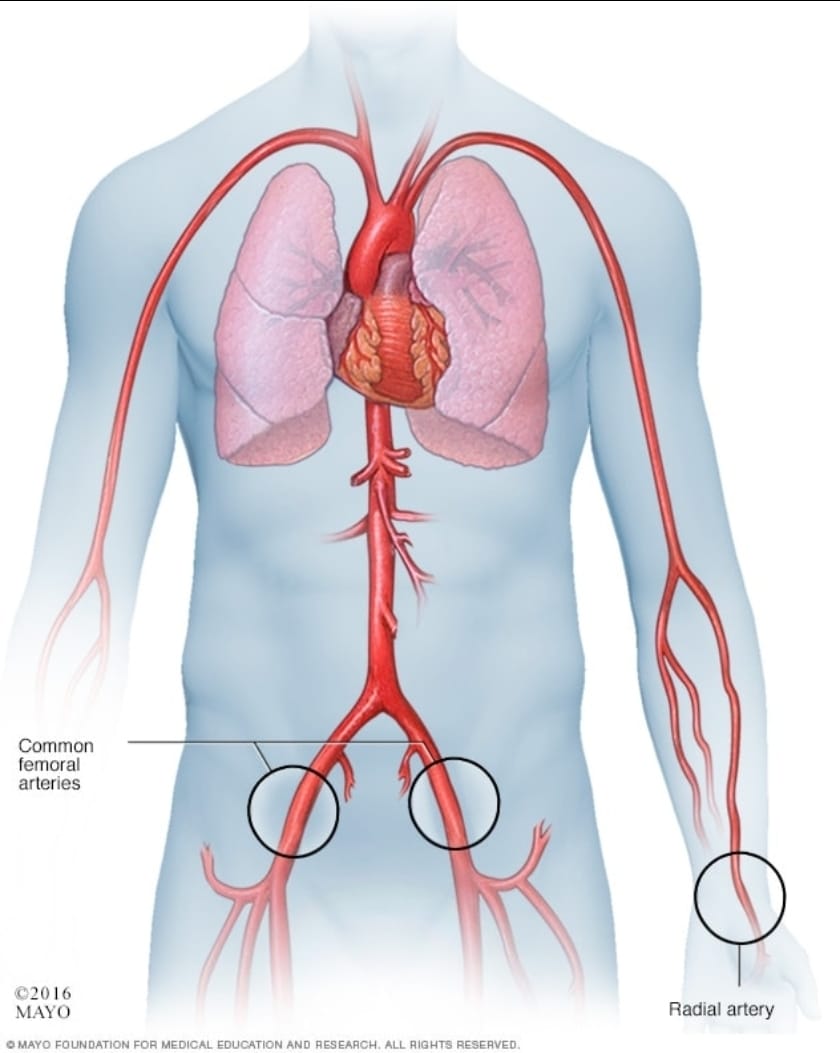

وتهدف عملية مجازة الشريان التاجي إلى إعادة توجيه تدفق الدم حول الانسداد الذي يعيق وصوله إلى القلب. وفي هذه الحالة، تم إدخال الأدوات الجراحية وتمريرها عبر وعاء دموي في ساق المريض، بدلاً من فتح القفص الصدري، وفقاً لتقرير علمي نُشر في مجلة Circulation: Cardiovascular Interventions.

إنجاز طبي غير مسبوق: إجراء أول عملية مجازة للشريان التاجي دون شق الصدر، عبر تقنية تدخلية دقيقة من خلال الأوعية الدموية، ما يفتح آفاقاً جديدة لجراحات القلب الأقل إيلاماً والأكثر أماناً.